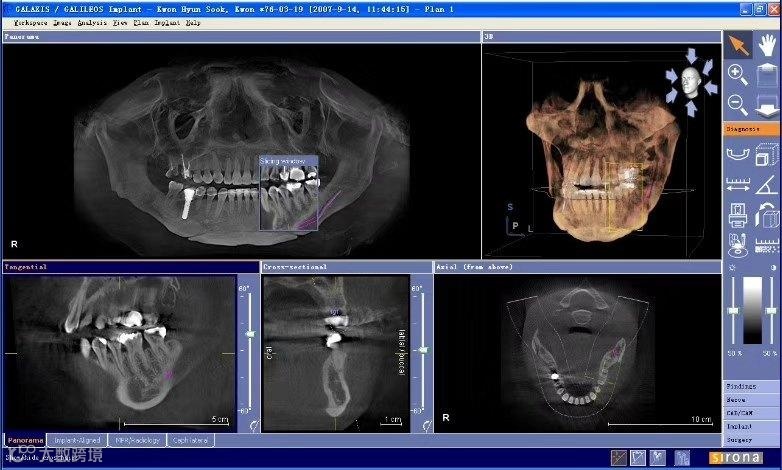

口腔CT,医学上常称为锥形束CT(CBCT)。它与传统的大影像科CT原理类似,但辐射剂量更低、扫描速度更快、对牙齿和骨骼的显像精度更高。

您可以把它想象成一个为您的口腔和颌面区域拍摄的“三维立体高清照片”,医生能借此360度清晰地观察牙根、颌骨、神经管等重要结构,这是普通牙科X光片无法实现的。

种植牙规划

就像盖楼前要勘探地质一样,种植前先通过CT精确测量牙槽骨的高度、宽度和密度,并避开重要的神经和血管,确保手术万无一失。